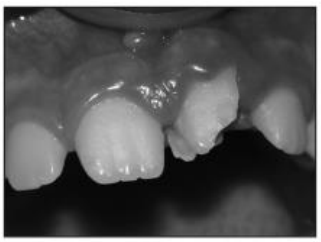

Considere a imagem, a seguir:

A imagem, acima, representa: